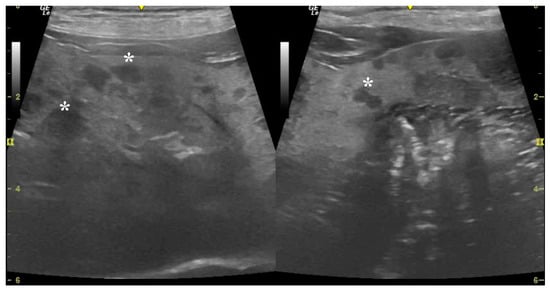

3.2. Ultrasound Examination

| Lesion homogeneity | <0.001 | ||

| Homogeneous (n (%)) | 30 (93.75) | 1 (9.09) | |

| Heterogeneous (n (%)) | 2 (6.25) | 10 (90.90) | |

| Lesion echogenicity | <0.001 | ||

| Hyperechoic (n (%)) | 2 (6.25) | 0 (0) | |

| Hypoechoic (n (%)) | 29 (90.62) | 3 (27.27) | |

| Heteroechoic (n (%)) | 1 (3.12) | 8 (72.72) | |

| Maximum lesion diameter (cm) (mean SD) | 1.23 (0.68) | 4.33 (1.52) | <0.001 |

| Average lesion diameter (cm) (mean SD) | 0.64 (0.42) | 2.6 (1.03) | <0.001 |

| Hepatobiliary ultrasound score | <0.001 | ||

| Moderate (score 3–5) (n (%)) | 30 (93.75) | 0 (0) | |

| Severe (score 6–12) (n (%)) | 2 (6.25) | 11 (100) |